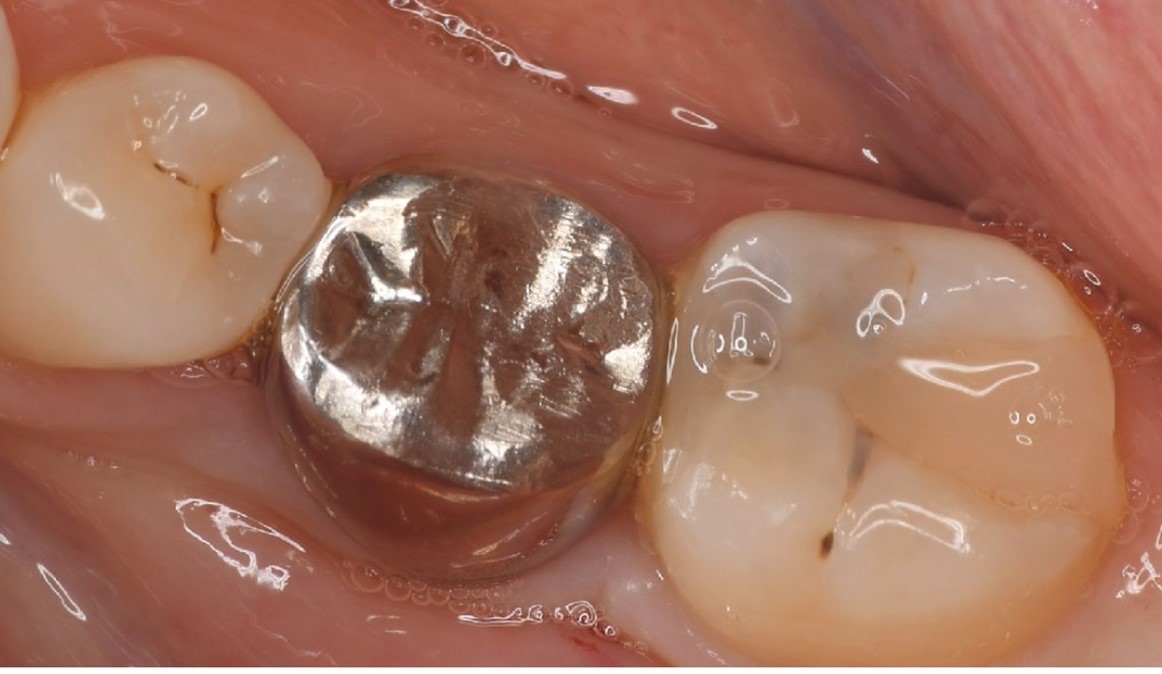

A 27-year-old female patient came to us with discomfort in the right lower jaw (Figure 1). Her primary symptoms were pain in the lower right tooth when biting and discomfort associated with not being able to chew well with the lower left single denture. The patient was married and had one young child, and previously received dental treatment in China, then had returned to Japan for childbirth and early childcare. The patient was a nonsmoker with moderate plaque control and medical history taking revealed no problems. In clinical and radiographic examinations, a root fracture was observed on tooth #46, which had been endodontic ally treated and restored with a full-cast metal crown. Periodontal probing revealed a pocket depth of 8 mm on the buccal center side of the tooth. No pain was detected with percussion and mobility of the tooth was normal. (Figure 1, Figure 2, Figure 3).

Figure 3.Preoperative intraoral findings. A metal crown was inserted at #46 and bleeding on probing during the periodontal pocket examination was noted.

Full metal crowns were inserted for #46 and #47. Pathological mobility and bleeding on probing were not seen, and the transplanted tooth showed good function.

Figure 7.Inter-oral photo obtained after treatment. Full metal crowns were inserted for #46, #47. Pathological mobility and bleeding on probing were not seen, and the transplanted tooth showed good function.